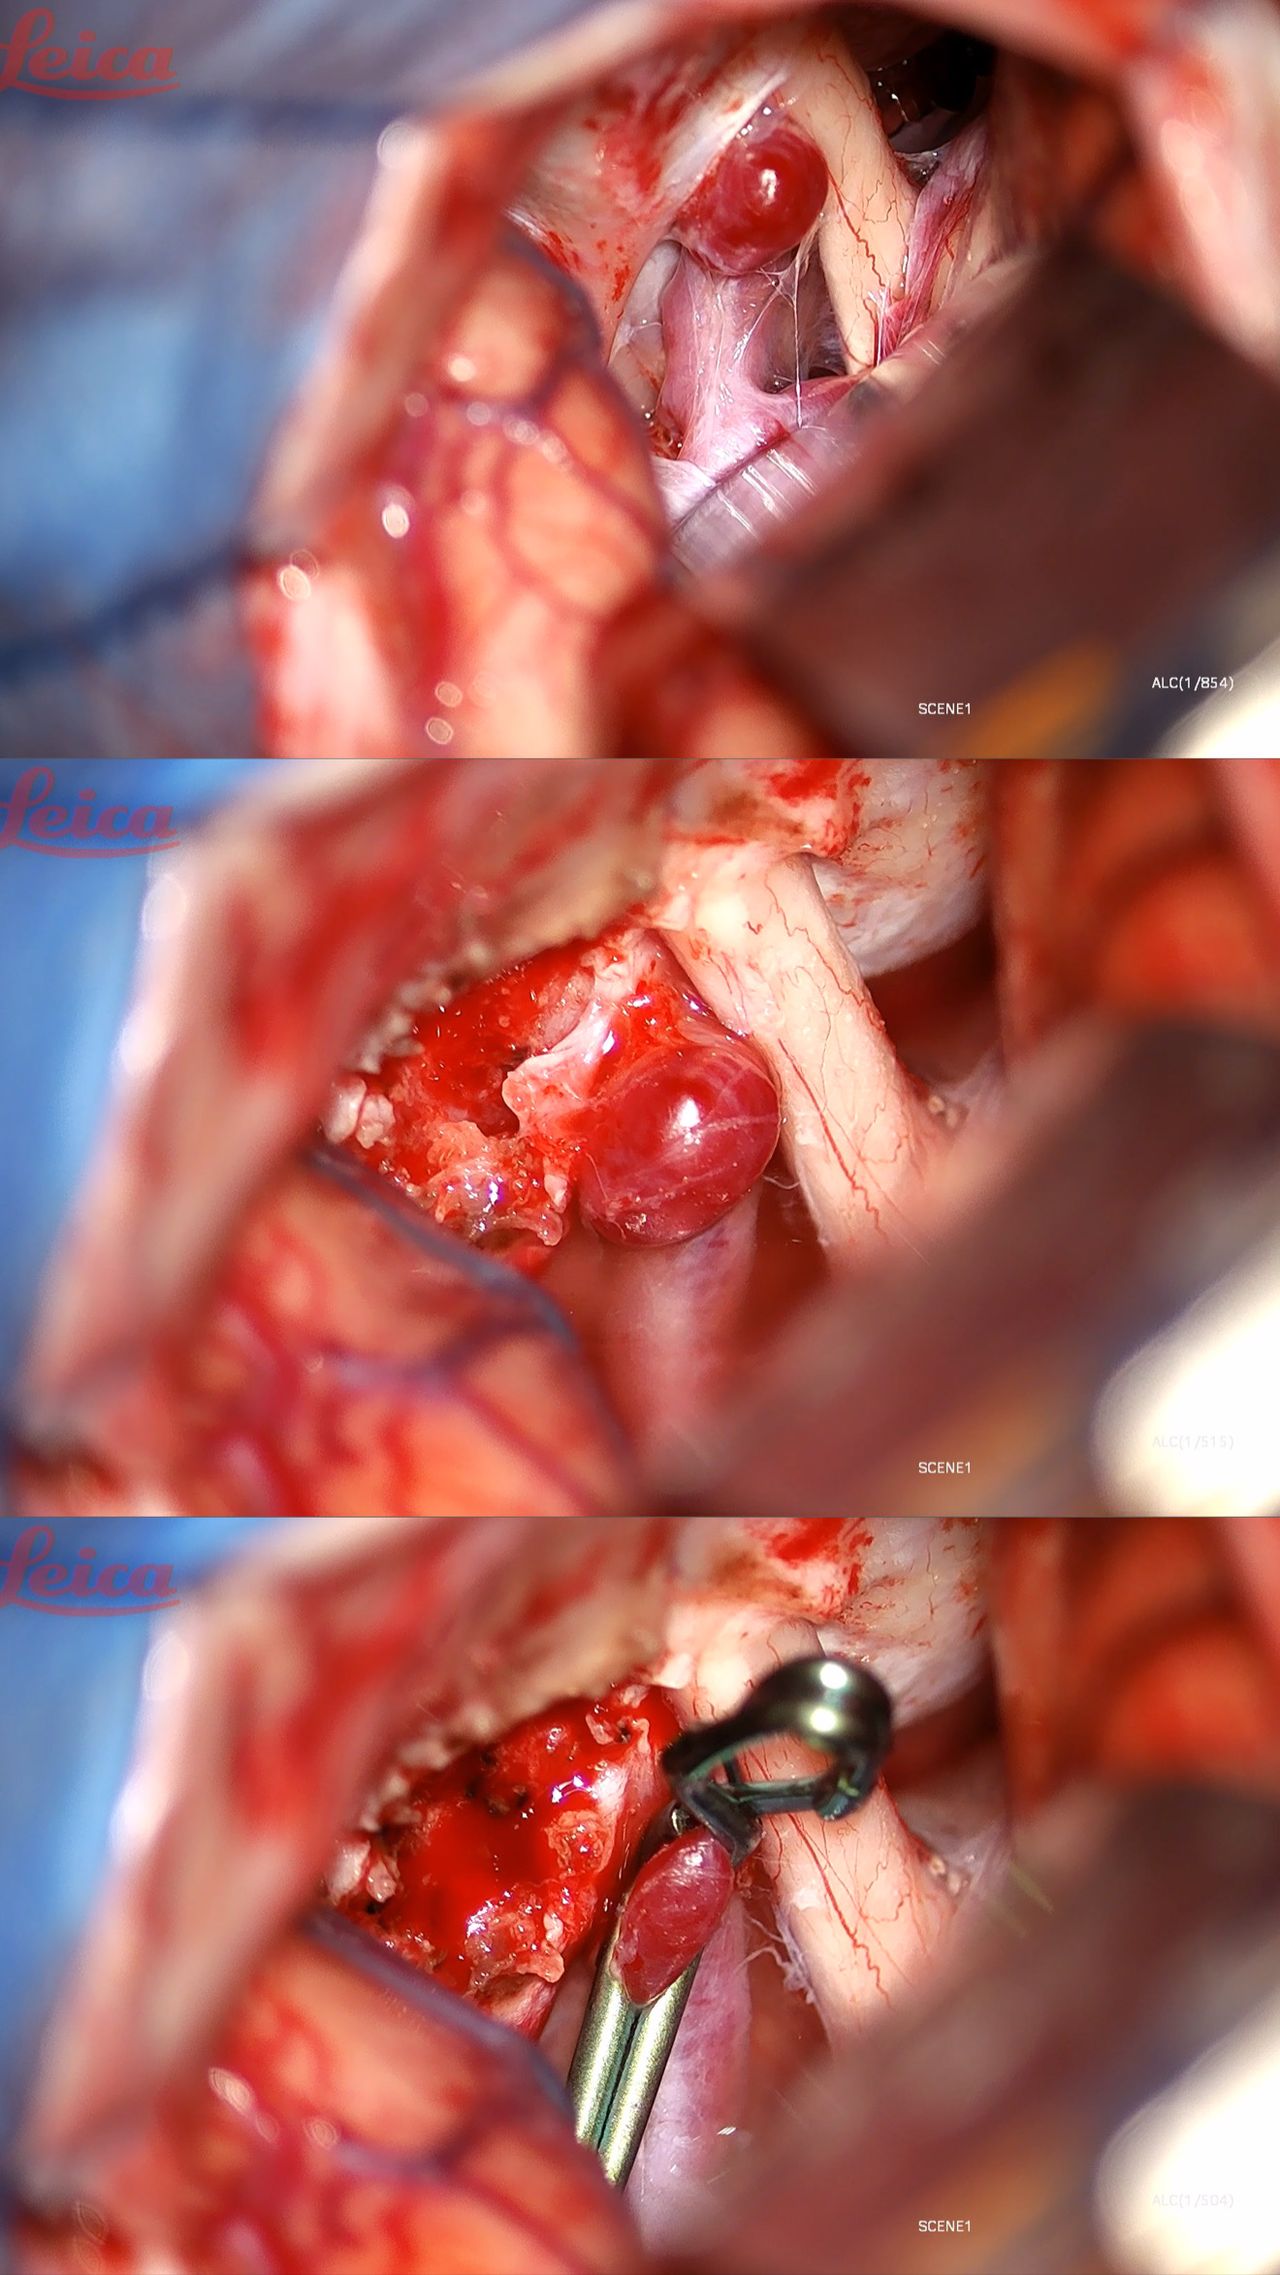

• Use of the Median Sulcus Entry Zone for Microsurgical Resection of a Ruptured Cavernous Malformation of the Pons: A 2-Dimensional Operative Video

• Midbrain Cavernous Malformation: Microsurgical Nuances and an Anatomoclinical Review 2-Dimensional Video

• Microsurgical Resection for Cavernous Malformation of the Uncus: 3D-Operative Video